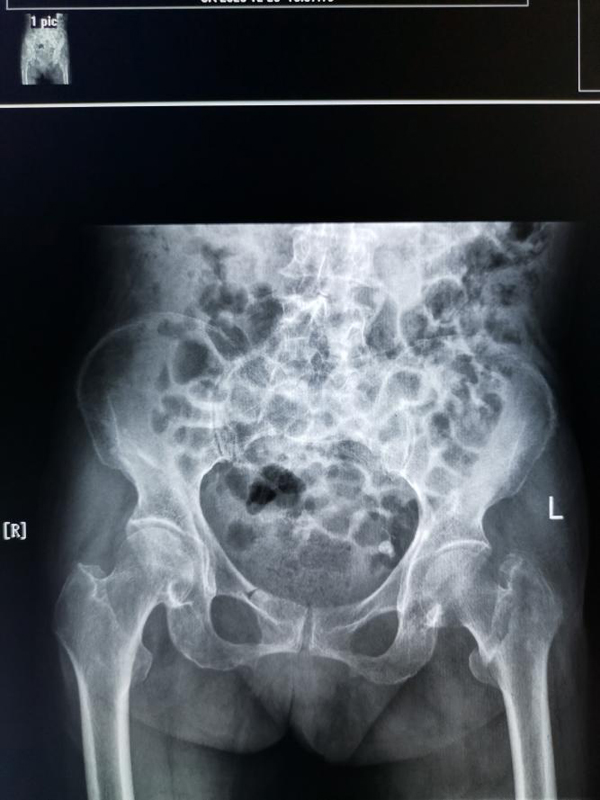

两个多月前,82岁的孙奶奶因“摔伤致左髋部疼痛伴活动受限6小时”入住陕西省核工业二一五医院创伤骨科,入院后拍X线片示:左侧股骨粗隆间骨折。查体:左下肢外旋90度,活动受限,患肢肌力可,余无明显异常。通过询问得知,孙奶奶既往30年前诊断为高血压,10年前又患脑梗死,同时合并有高血压、低蛋白血症、肾功能不全、慢性支气管炎并肺气肿等多种疾病,全身各脏器功能储备差,术中容易出现心、脑血管意外导致死亡。考虑到孙奶奶年事已高,加之其复杂的身体状况,接诊的杨萌国医生立即通知郭永良主任,并向医院上报重大手术。

术前三维CT: